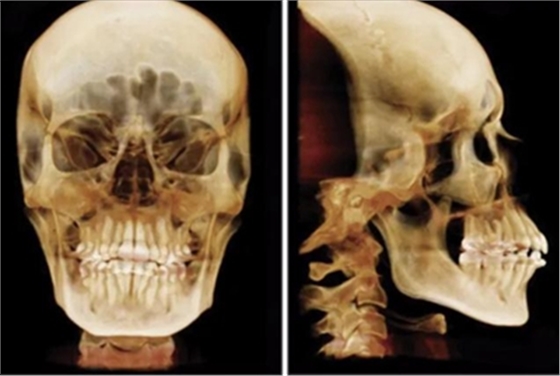

患者曾行正畸治療,現(xiàn)覺笑容不美觀前來就診。患者正面觀及側(cè)貌示下頜發(fā)育不足,偏高角,唇閉合不全。上下頜中線齊。覆合、覆蓋4毫米。磨牙關(guān)系及尖牙關(guān)系II類。上頜擁擠度4mm,下頜擁擠度6mm。4顆第一前磨牙在第一次正畸治療時已拔除。上下牙弓呈尖圓型,牙弓狹窄。

頭影測量分析,SNA角84°,ANB角6°,高角型,詳見下表。

同時,由于患者存在著牙弓狹窄,為了在解決擁擠的同時解決牙弓狹窄問題,手術(shù)輔助的快速擴弓是一個較好的選擇。手術(shù)輔助的上、下頜擴弓,可以同時解決前牙段擁擠,內(nèi)收上前牙,減小覆蓋。

因此最終,我們決定采用手術(shù)輔助快速擴弓進行上下頜擴弓,上頜行腭中縫切開術(shù)、下頜行正中劈開后使用hyrax擴弓器進行擴弓。擴弓完成后再使用固定矯治器進行矯正。

全麻下進行上頜骨腭中縫骨皮質(zhì)劈開及下頜正中劈開術(shù)。手術(shù)后,用X光片檢查上頜骨和下頜骨中線切口的位置和方向。